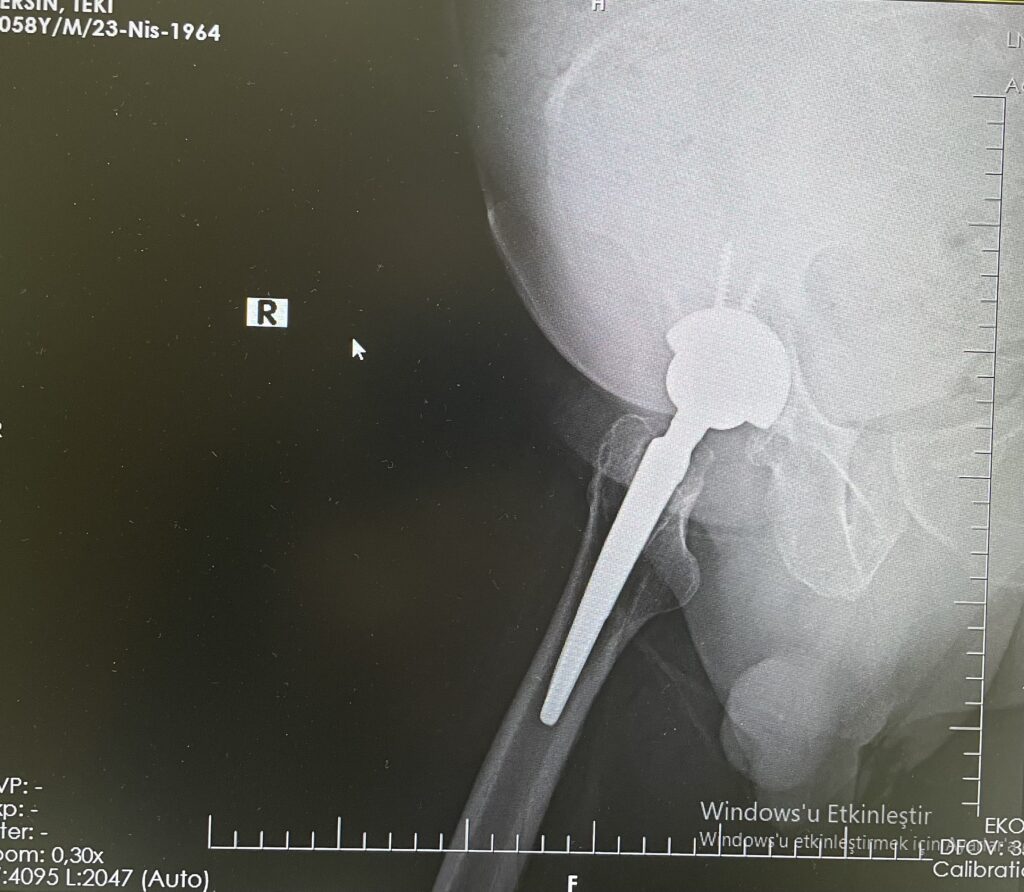

E.T.